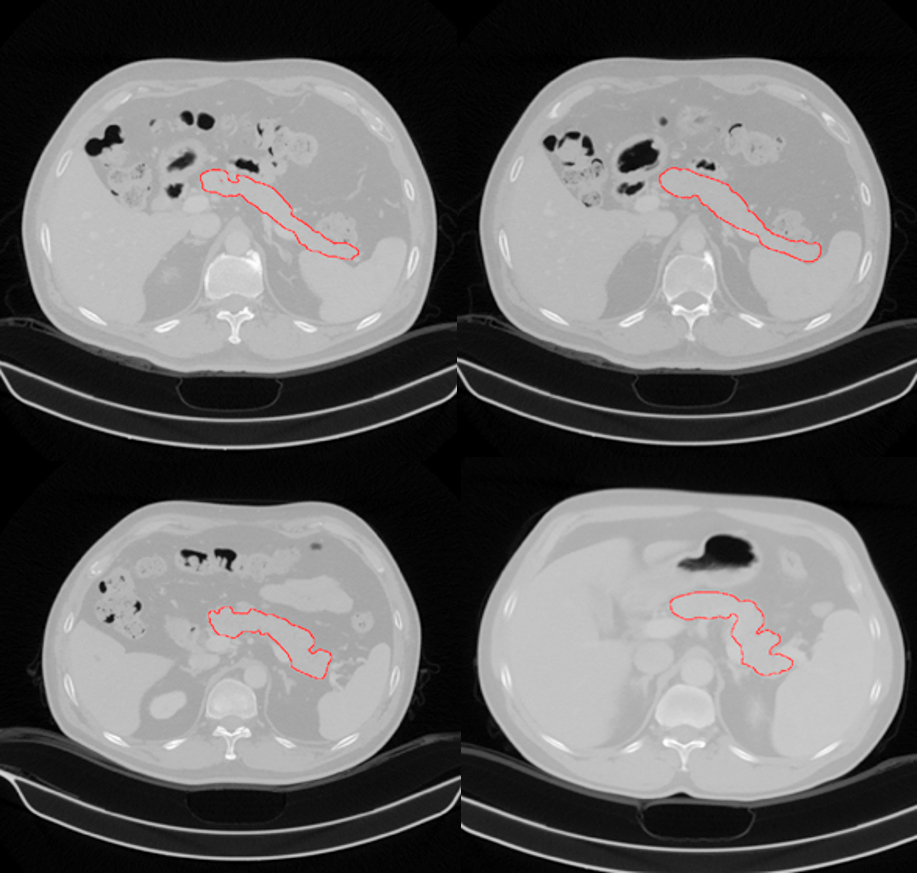

描红部分为王一达团队找出的胰腺位置